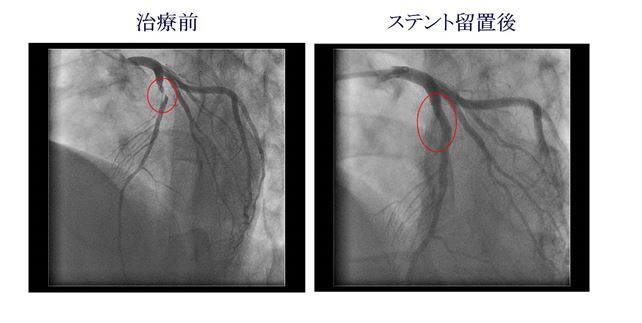

狭窄、又は閉塞した冠動脈を拡張するカテーテル治療をPCIと呼びます。カテーテルの先端を冠動脈の入り口に挿入し、カテーテルの中から冠動脈にワイヤーを通し、それに沿ってバルーン(風船)を挿入し、冠動脈を拡張します。ほとんどの場合、バルーンで拡張後にステントと呼ばれる金属のパイプを留置して、しっかり拡張します。治療時間は1-2時間です。PCIの件数は年間180-200件です。その他ローターブレーターという器具を用いて血管内を削る治療も行っています。